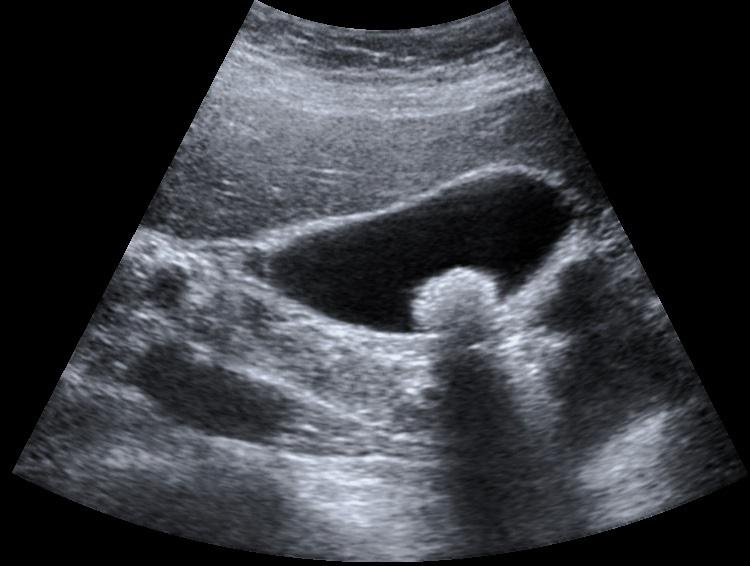

Evalina noticed noticed a pull in the right flank area, not knowing what the issue was until she had a ultrasound to discover it was her gallbladder causing the pain.

Before my gall bladder surgery 3 years ago I actually thought I had pulled a muscle in my right flank area, radiating to the lower back.  This went on for some time with no relief before I discovered through ultrasound that my gallbladder was the culprit.  During surgery not only was it full of stones, but also full of tunnels, it was actually disintegrating!  I had immediate relief of pain afterwards but for a month I was so nauseated I couldn't eat and lost12 pounds.  Gradually that abated and all was well. But over time I had problems that I attributed to IBS.  Bloating, gas, digestive issues, cramping, elimination issues.